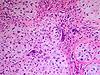

CASO N° 1 (Dr. Jair e Dr. Delgado)

Paciente do gênero masculino, 44 anos de idade, apresenta uma lesão no palato duro e palato mole.